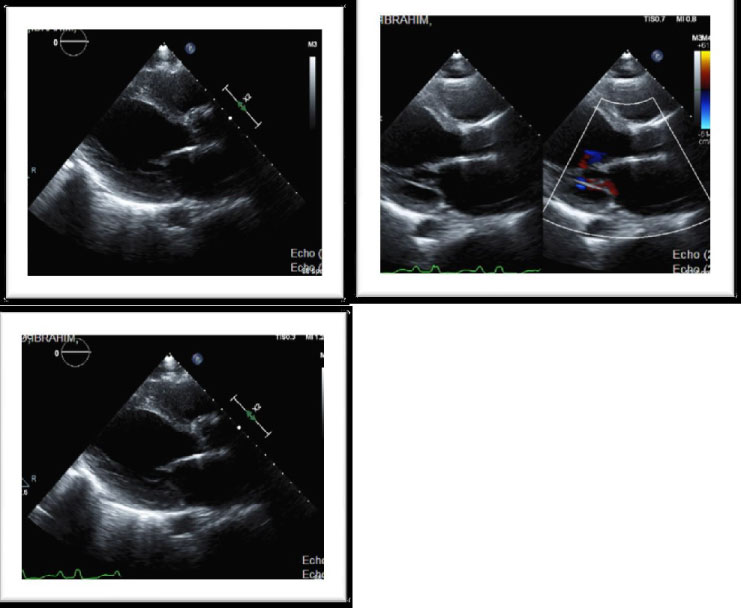

Echocardiogram: moderate dilation of the left ventricle with severely impaired LV systolic function, LVEF = 30%. Akinesia of basal and mid Inferolateral wall, mid-septum, Septo-basal, mid-lateral, mid-inferior and Infero-basal wall. Grade I abnormal diastolic relaxation, left atrial mild dilated. Normal pulmonary arterial pressure (Figures 1). Lower extremities venous Doppler study was unremarkable.

Figure 1: Moderate dilation of the left ventricle with severely impaired LV systolic function LVEF = 30%. Akinesia of basal and mid Inferolateral wall, mid-septum, Septo-basal, mid-lateral, mid-inferior and Infero-basal wall GIDD. View Figure 1